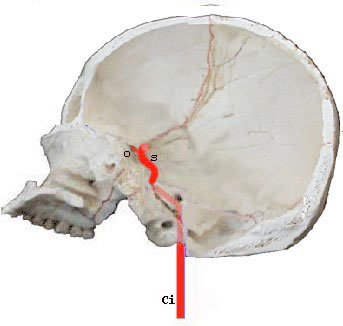

Base endocrnienne

-B: Bulbe

-b: tronc basilaire

-ci: carotide interne

-ma / mm / mp: artres mninges ant., moy. et post.

-o: artre ophtalmique

-s siphon carotidien

Polygone de Willis trac autour du losange opto-pdonculaire

Le polygone baigne dans l'espace sous-arachnodien que constitue la citerne opto-chiasmatique. Les communicantes postrieures reposent sur les lames dure-mriennes reliant les apophyses clinodes de chaque ct.

Lartre carotide interne irrigue la partie antrieure du cerveau ainsi que lorbite et son contenu.

Elle se dgage de la carotide primitive la hauteur du cartilage thyrode, niveau correspondant la quatrime vertbre cervicale.

Son trajet vers la cavit crnienne est trs sinueux. En effet, elle transite par le canal carotidien creus dans le rocher en dcrivant deux coudes, devient intracrnienne en pntrant dans le sinus caverneux au sein duquel elle longe le flanc du sphnode, puis elle en merge en marquant un dernier coude qui loriente en arrire et en haut (siphon carotidien=s) et se termine en dedans de la clinode antrieure, laplomb de lespace perfor antrieur. Son calibre est de 9mm en moyenne.

De la convexit antrieur du siphon se dtache son unique collatrale, lartre ophtalmique (o).

Elle se rsout en quatre artres terminales: les crbrales antrieure et moyenne, la chorodienne antrieure et la communicante postrieure.